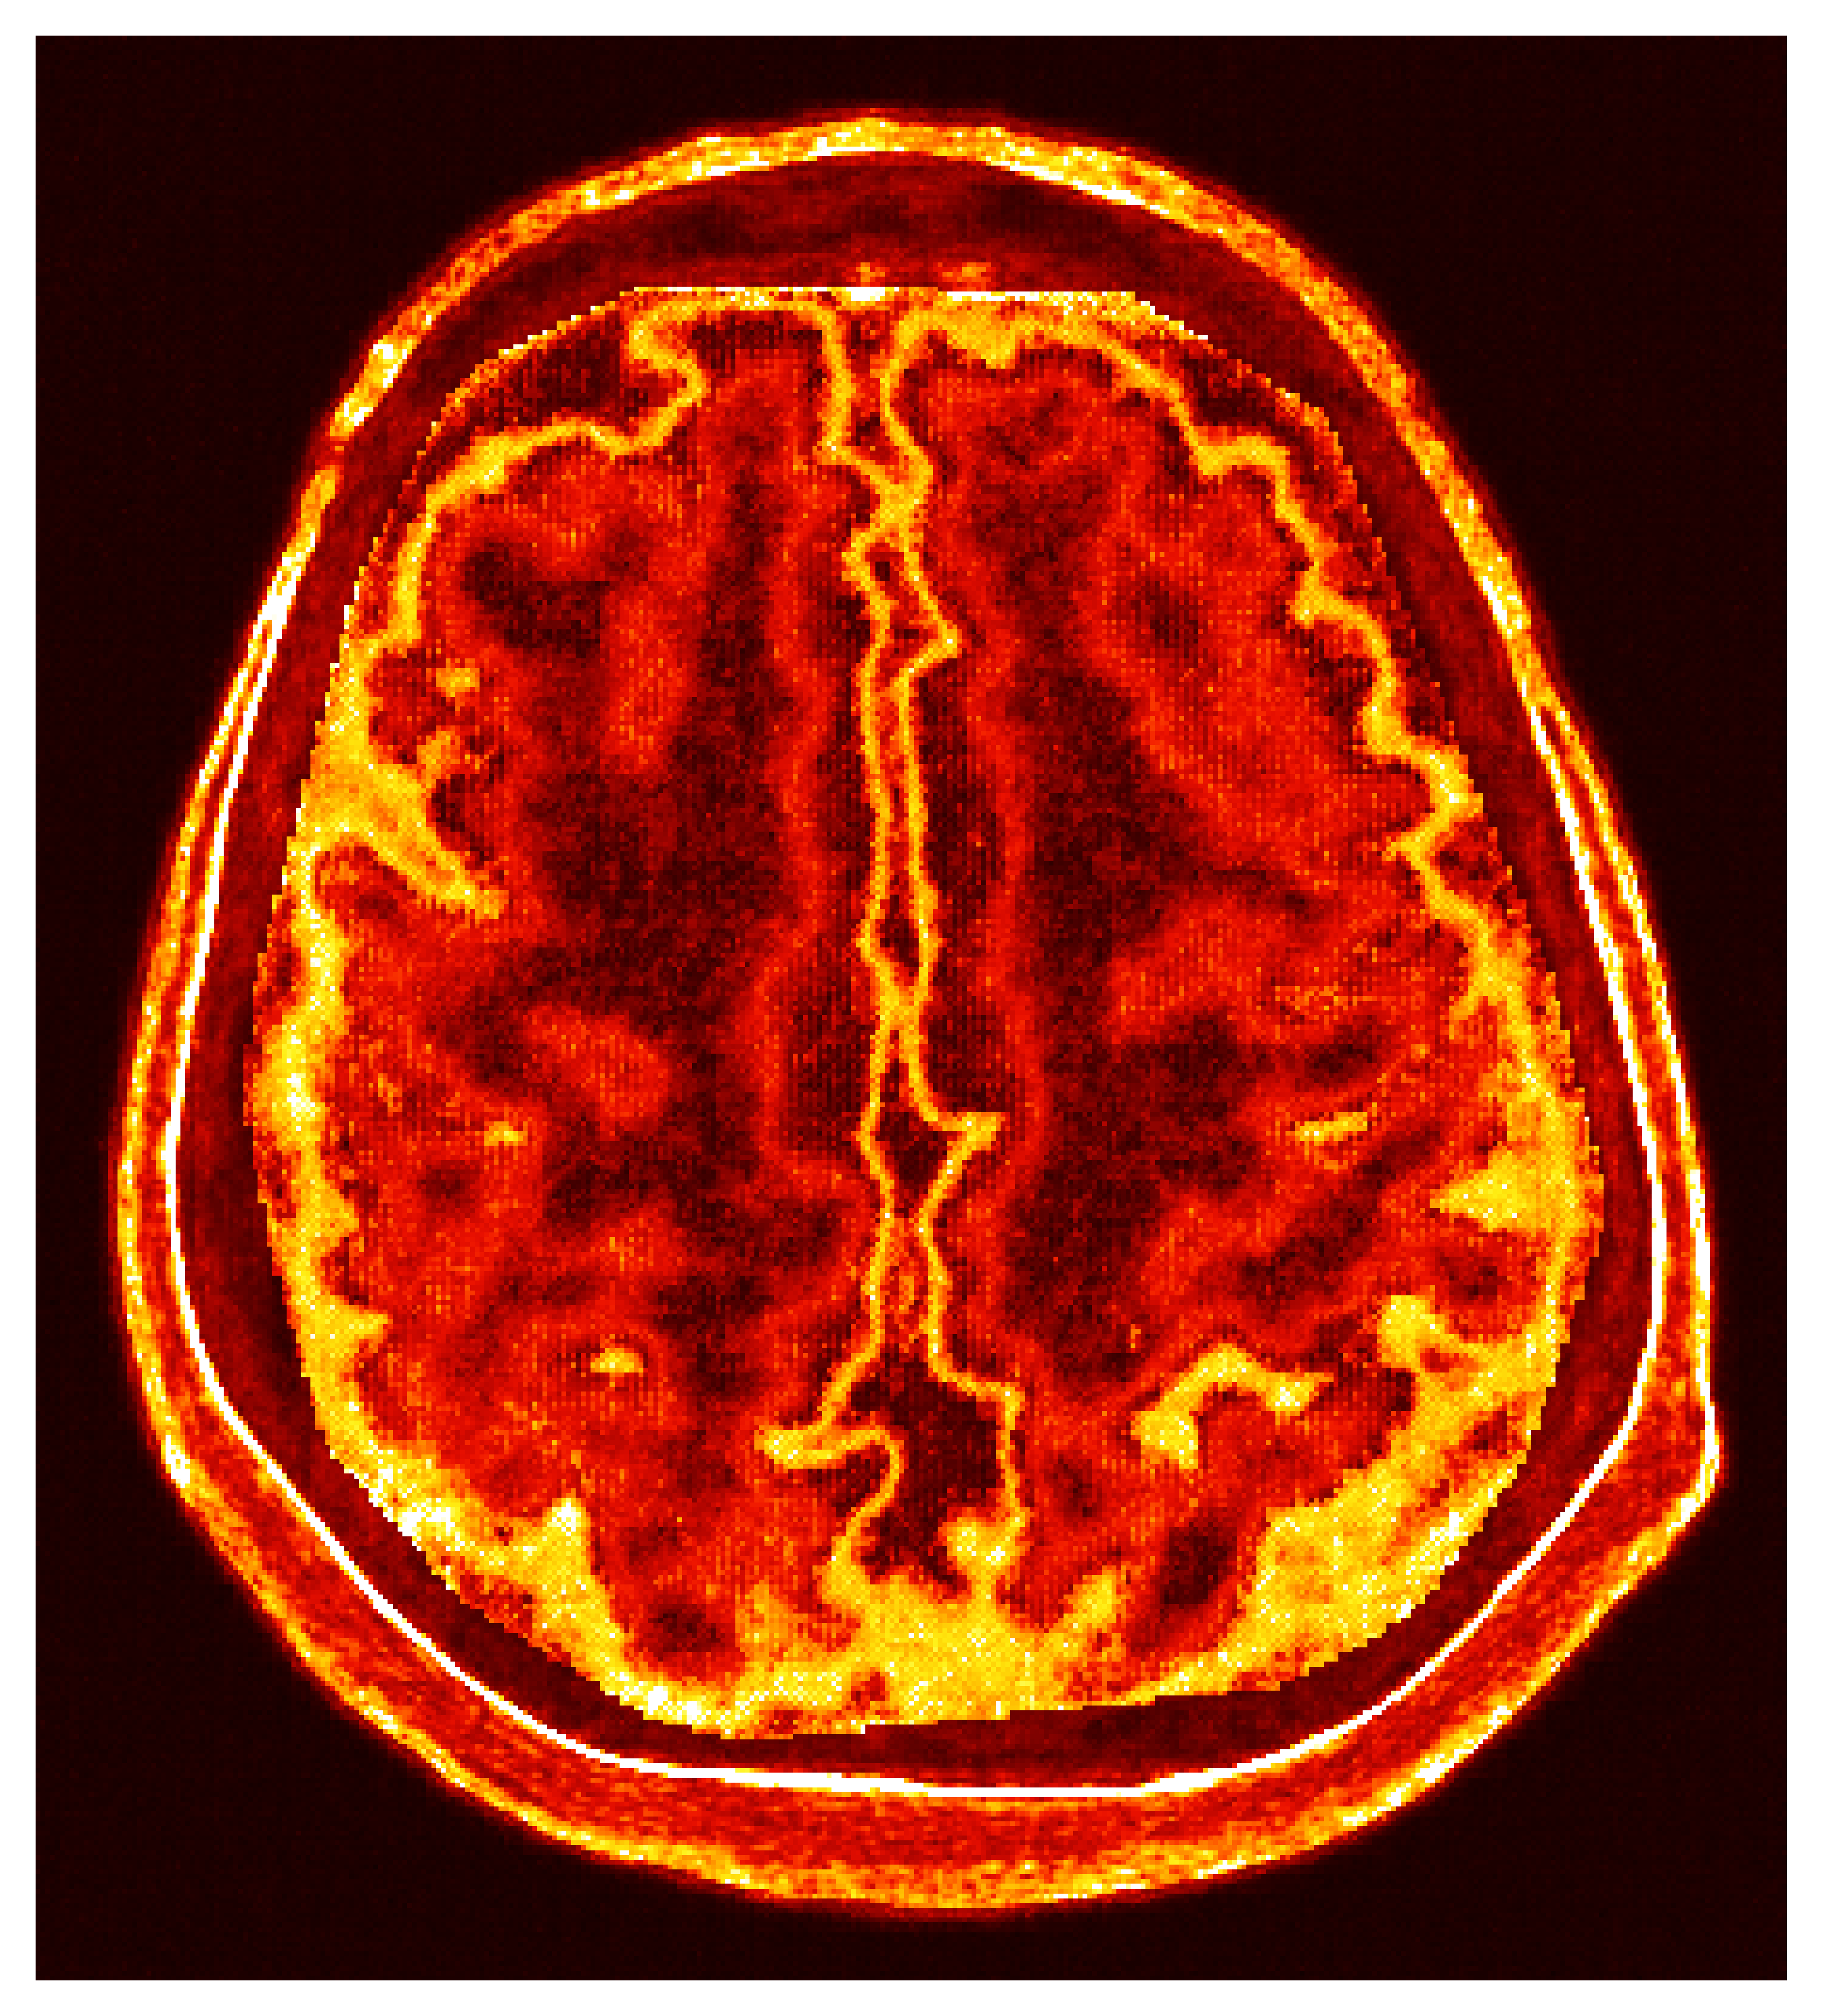

Inverse problems are fundamental to numerous scientific and engineering fields, wherein one seeks to infer causative factors from observable effects. The central challenge in inverse problems is that they are often ill-posed; the solutions may not exist, be non-unique, or depend discontinuously on the data. This ill-posedness demands sophisticated mathematical techniques to ensure stable solutions and to explore the family of solutions that can explain the data. The example we treat practically involves challenging medical imaging, where internal structures of the human body (the brain) are inferred from ultrasound measurements through the skull seen in Figure 1. The importance of fast and reliable solutions in this application cannot be overstated as they directly influence possibly life saving diagnostic decisions.

Transcranial Ultrasound Computed Tomography (TUCT) is a non-ionizing, non-radiative imaging modality that creates images of brain tissue from measurements of impinging ultrasound waves due to contrast in tissue acoustic properties. Unlike other ultrasound imaging targets, like breast imaging [44, 45], TUCT faces the challenge of high acoustic contrast in the cranial bone, leading to scattering unsuitable for traditional traveltime tomography methods [46]. Tomographic methods require high frequencies for higher resolution imaging, but attenuation through the skull is exacerbated at higher frequencies thus preventing high-resolution imaging when relying on traveltime methods. This challenge has hindered ultrasound’s application to brain imaging until recent developments when [47] identified that similar challenges exist in transcranial ultrasound imaging as with sub-salt imaging used by exploration seismology. The main reason seismic techniques are capable of imaging through high-acoustic contrast salt is because these sophisticated inversion methods model the full physics of the wave equation to make sense of the scattered waves. Whereas traditional ultrasound only uses arrival times, seismic imaging techniques model all waveforms allowing for higher effective resolutions at lower frequencies that experience less attenuation through the skull. These methods are denoted Full-Waveform Inversion (FWI) since they model and match the full observed waveform, see Figure 6 for an example of the full waveform.

The first step of implementing ASPIRE concerns obtaining samples from a realistic prior for the target parameter vector , in this case, gridded velocity parameters of human brains and skulls. The parameters collected in the MIDA dataset [56] correspond to a single 3D volume for the acoustic velocity collected from a single subject and will unfortunately not be appropriate to train a neural model that will generalize to other human patients. As far as we know, there is no dataset that includes acoustic velocity collected from many patients, so we made our own dataset based off the multi-subject FASTMRI dataset [57]. This custom dataset, detailed in Section \thechapter.A, comprises N=1000 diverse acoustic velocity parameters collected from different human patients, . This size of datasets facilitates generalization of the amortized posterior sampler across different datasets collected from unseen patients. The dataset is accessible via the repo ASPIRE.jl.

Based off of the MRI dataset [57], we manually assigned acoustic values to MRI intensities by following the table of acoustic brain tissue properties in the supplemental section of [47]. Although MRI intensities are not necessarily related to acoustic tissue properties, we found that we could produce reasonably realistic acoustic parameters as compared to the acoustic parameters from the MIDA volume. In Figure 19, we show some example training acoustic parameters. We also plot the average and standard variation between all 1000 training samples in Figure 20. From these plots, we note that there are few similarities between training examples apart from the biologically consistent human brain structures.